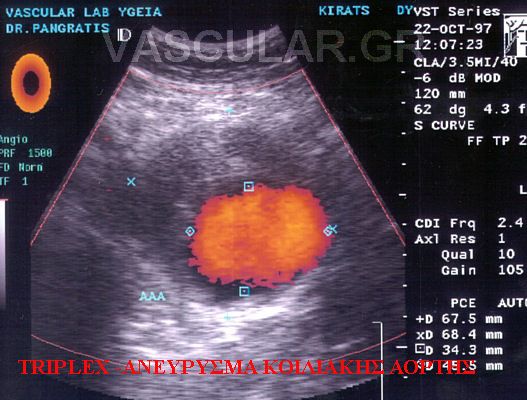

Ôï ìÝãåèïò ôùí áíåõñõóìÜôùí êõìáßíåôáé áðü Ýíá ðïñôïêÜëé Ýùò êåöáëÞò åìâñýïõ.

Åíôüò ôïõ áíåõñõóìáôéêïý óÜêïõ õðÜñ÷ïõí óõíÞèùò èñüìâïé êáé õðïëåéììáôéêüò áõëüò, åíþ åîùôåñéêÜ ìðïñåß íá õðÜñ÷åé öëåãìïíþäçò ðåñéáíåõñõóìáôéêÞ áíôßäñáóç ìå áðïôÝëåóìá íá ðñïóêïëëÜôáé ü÷é ìüíï ç êÜôù êïßëç öëÝâá áëëÜ êáé ôï äùäåêáäÜêôõëï Þ ôï ëåðôü Ýíôåñï.

ÓõíÞèùò ç äéÜãíùóç ôïõ áíåõñýóìáôïò ãßíåôáé ôõ÷áßá ìåôÜ áðü êÜðïéá äéáãíùóôéêÞ åîÝôáóç üðùò áêôéíïãñáößá óôçí êïéëéÜ, áîïíéêÞ Þ ìáãíçôéêÞ ôïìïãñáößá êïéëßáò êáé êõñßùò áðü õðåñç÷ïãñÜöçìá Triplex , åéäéêüôåñá äå ìåôÜ áðü áããåéïãñáößá Þ õðåñç÷çôéêÞ ðáíáñôçñéïãñáößá.

Ï êßíäõíïò ñÞîåùò ôïõ áíåõñýóìáôïò Ý÷åé ó÷Ýóç ìå ôï ìÝãåèïò ôïõ áíåõñýóìáôïò. ¸ôóé óå ìåãÜëá áíåõñýóìáôá äéáìÝôñïõ 6-7cm ï êßíäõíïò ñÞîåùò åßíáé 45-50% åíôüò ìßáò äåêáåôßáò. Åíþ óå ìéêñÜ áíåõñýóìáôá ìéêñüôåñá ôùí 5cm ï êßíäõíïò ñÞîåùò åßíáé 15-20% óôçí ßäéá ÷ñïíéêÞ ðåñßïäï.

Õðåñç÷çôéêüò Ýëåã÷ïò triplex åðéâÜëëåôáé óå üëïõò ôïõò áóèåíåßò ðïõ ðáñïõóéÜæïõí éóôïñéêü, ìå éó÷áéìéêÜ óõìðôþìáôá Þ êëéíéêÜ åõñÞìáôá éó÷áéìßáò Üêñùí êáé ïñãÜíùí, êáñùôéäéêÞ óôÝíùóç óõìðôùìáôéêÞ – áóõìðôùìáôéêÞ, õðÝñôáóç Þ óôåöáíéáßá ðÜèçóç, éó÷áéìßá êÜôù Üêñùí êáé ýðáñîç óõããåíïýò ðñþôïõ âáèìïý ìå áíåýñõóìá ôçò êïéëéáêÞò áïñôÞò (ÁÊÁ).